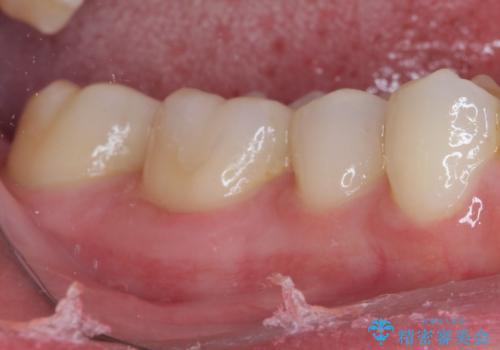

銀歯をセラミックにしたい セラミックインレー修復

そして次の来院時、セラミックインレーを装着し、噛み合わせなどの調整を行います。

それを左右に分けて行いました。

自然な色調で大変満足されました。